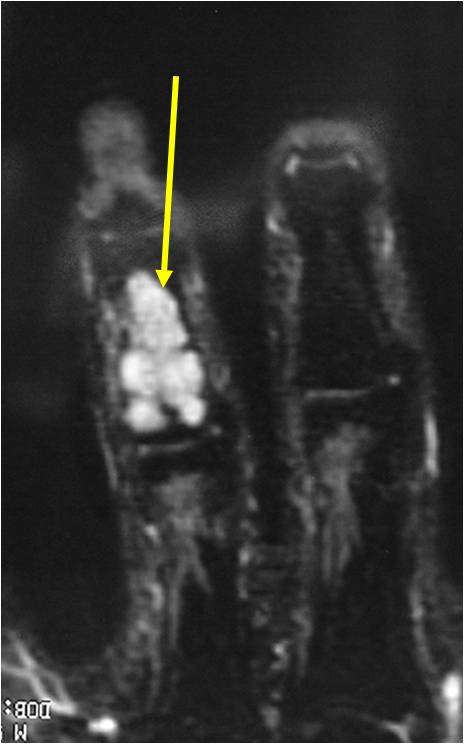

- MRI

- Lobulated margin

- Marked increased intensity long TR images

- Calcified chondroid – low intensity all sequences

MRI:

- Lobulated margin (Lobular Growth Pattern)

- T1 Weighted Images: Intermediate Signal Intensity

- Calcifications will be low signal

- T2 Weighted Images: High Signal Intensity

- High water content shows as high signal on T2 weighted images